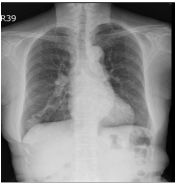

14. 69 years female, recurrent purulent sputum